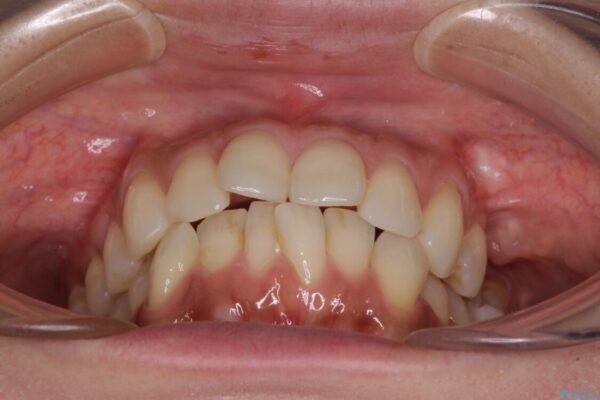

全体的なデコボコと、以前抜歯した歯のスペースを閉じた部分が気になるとのことで来院された患者様です。

左上第一大臼歯を抜歯した際に、スペースを閉じたそうですが、歯が傾斜してものが挟まって不快とのことでした。

インビザライン矯正で全体の歯列と整えるとともに、左上第一大臼歯部にはスペースを作り、インプラントによる補綴治療を行うこととしました。

治療前

• インビザラインによる矯正治療と奥歯のインプラント治療 治療前画像